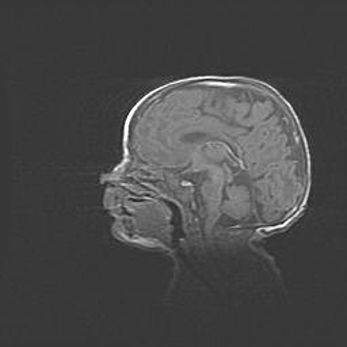

Мальформация Денди-Уокера. Киста задней черепной ямки.

Агенезия мозолистого тела.

Возраст: 2,5 месяца

Вес: 2420 г

Пол: женский

Окружность головы: 37 см

Срок гестации: 32 недели

Мальформация Денди—Уокера — редкий вид патологии ЦНС, представляющий собой врожденный порок развития каудального отдела ствола и червя мозжечка, ведущий к неполному раскрытию срединной (Мажанди) и латеральных (Лушка) апертур IV желудочка мозга. Для этогно синдрома характерна триада симптомов: гипотрофия червя мозжечка и/или полушарий мозжечка, кисты задней черепной ямки, гидроцефалия различной степени. В 70% случаев порок сочетается и с другими аномалиями головного мозга, в частности с агенезией мозолистого тела.